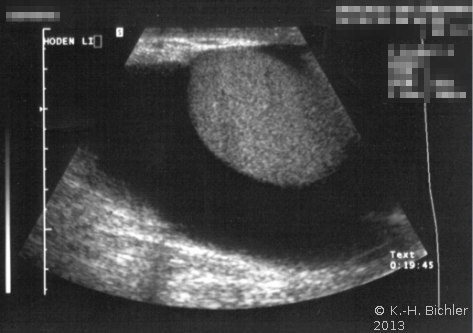

Die Abbildungen zeigen kindliche Hydrozelen (primäre) bzw. eine im Erwachsenenalter unklarer Genese (Abbildung 4abc).

DiaphanoskopieDiaphanoskopieDie Diaphanoskopie ist eine einfache klinische Untersuchung zur Abgrenzung der Hydrocelen von anderen skrotalen Raumforderungen. Bei Aufsetzen einer Untersuchungslampe auf das Skrotum schimmert der flüssigkeitsgefüllte Raum rötlich, bei solidem Skrotalinhalt liese sich das Skrotum jedoch nicht durchstrahlen. sowie die Sonographie (Abbildung 5).